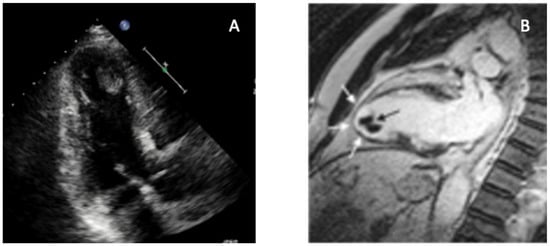

In addition to standardized lateral cephalometric radiographs, comprehensive assessment using dental cone-beam computed tomography (CBCT) and CT has become commonplace in the diagnosis and treatment of jaw deformities. Simulation based on cephalometr...